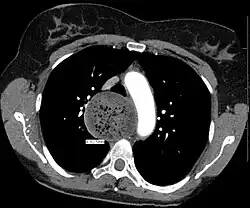

![]() | |

| A chest X-ray showing achalasia (arrows point to the outline of the massively dilated esophagus) | |